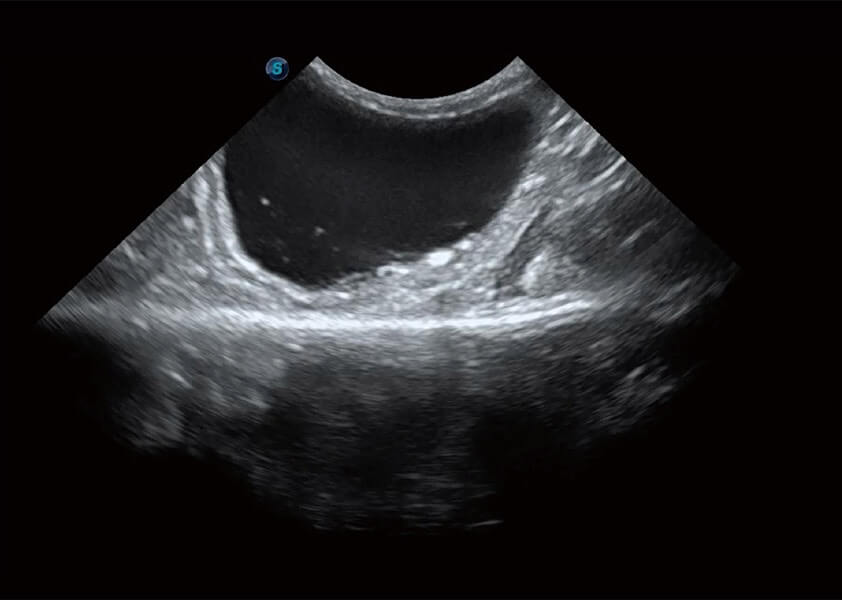

ProPet 60 作为一款高端台式动物超声设备,为动物医生的日常诊断提供了一系列贴合动物临床需求、解决临床实际问题的高级成像功能。凭借全系列高清探头,满足医生对腹部、心脏、生殖、浅表、肌骨等成像的所有需求,切实帮助您提升检查效率,提高诊断信心。

动物是人类最亲密的朋友和最值得信赖的伙伴。百老汇电子游戏官网也一直致力于探索动物专用的超声影像解决方案。 全新推出的ProPet系列,是百老汇电子游戏官网在动物超声影像智能化、专业化、精准化的一次跨越式革新。动物不能用言语来表述自己的不适,通过超声影像,ProPet系列搭建了动物医生与不同物种沟通的“桥梁”,为动物医生注入了“治愈之力”。